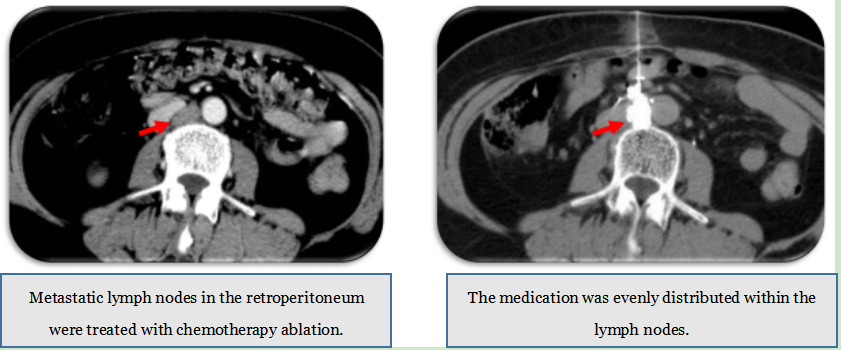

3. Tumor Chemotherapy Ablation